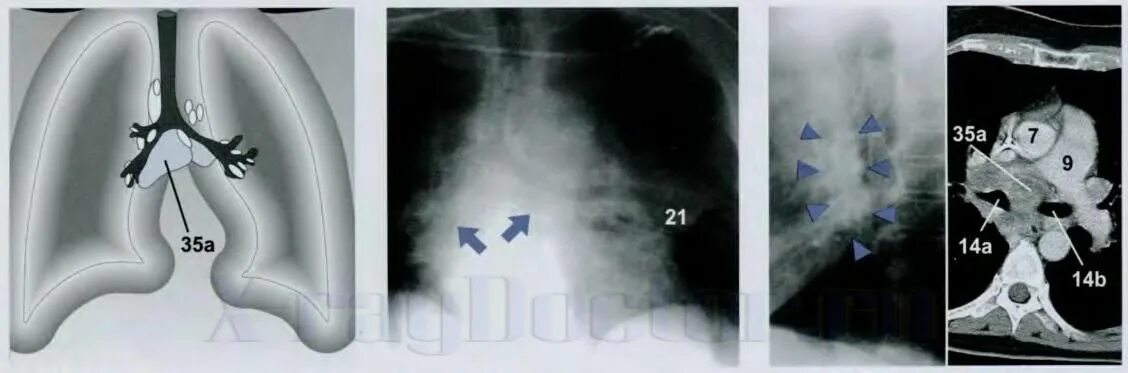

Метастазы плевры